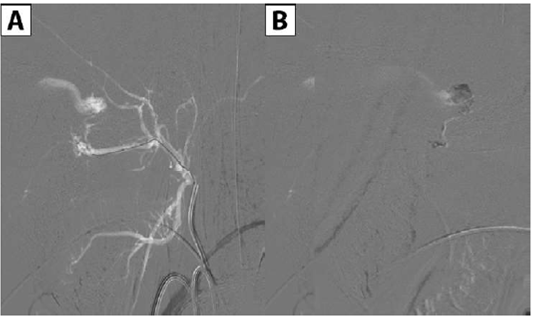

Se decidió realizar tratamiento endovascular mediante embolización con NBCA de las ramas aferentes de carótida externa.Se colocó vaina 4.5 F en arteria femoral derecha y se colocó catéter 4 F en carótida externa izquierda. Mediante sistema coaxial con microateterMagic 1.2 F ymicroguíaMirage 0.008 in.se logra acceder al pedículo principal de carótida externa proveniente de la arteria maxilar interna y se realiza embolizacióncon NBCA al 25% que llega a pie de vena logrando la oclusión del pedículo. El pedículo carótido hipofisario mide menos de 2 mm y no permite su cateterización supraselectiva, se decide nointentar tratarlo ya que se disminuyó notoriamente el flujo de la fistula y que en este momento creemos son mayores los riesgos que los beneficios de intentar embolizar dicho ramo. En los controles angiográficosse observa disminución del flujo y calibre de la vena oftálmica superior. No hubo complicaciones durante el procedimiento (Figura 4,Figura 5yFigura 6).

Figura 4:A)Imagénintra-procedimiento que muestra sistema coaxial con microguía y microcateter, con la punta de este último situada en inicio del ramo fistuloso de maxilar interna. B) Imagen intra-procedimiento en el momento de la inyección de NBCA en ramo fistuloso.

Figura 5:Angiografía digital post-procedimiento con inyección desde carótida externa izquierda que muestra oclusión completa de los ramos fistulosos procedentes de arteria maxilar interna.

Figura 6:Imagen post-procedimiento sin sustracción que muestra el agente embolizante (NBCA) inyectado en las ramas de maxilar interna izquierda. A)perfilB)frente.